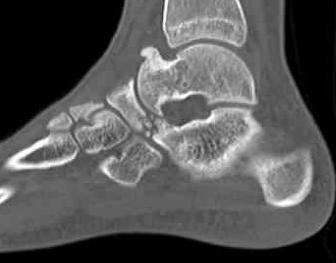

CT

TC coalition middle facet

Complete synostosis of the medial TC joint with OA of the posterior subtalar joint